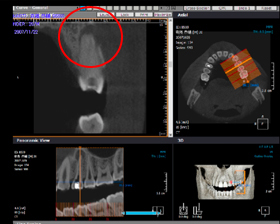

術後

CT画像(3次元)

インプラント埋入手術のCT断面画像です。

正確なインプラントサイズを術前に決定しますのでより安全、安心な手術が可能となりました。